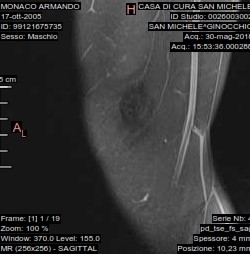

L'esame rm del ginocchio eseguito con apparecchio ad alto campo magnetico con acquisizioni multiplanari ha mostrato:

non evidenti alterazioni di segnale della spongiosa ossea a carattere focale o diffuso, conservata continuità e segnale delle corticali. Ampia incisura osteocondrale della superficie articolare esterna della troclea femorale estesa trasversalmente per 14mm e longitudinalmente per 12mm. Piccolo frammento osteocondrale in camera articolare anteriore sovrarotulea. Conservata morfologia e segnale del menisco laterale e del mediale senza apprezzabili lesioni a loro carico. Regolare continuità e segnale dei legamenti crociati, non evidenti segni di lesioni traumatiche in atto delle altre formazioni capsulo-legamentose esaminate, falda fluida intrarticolare, rotula in asse.